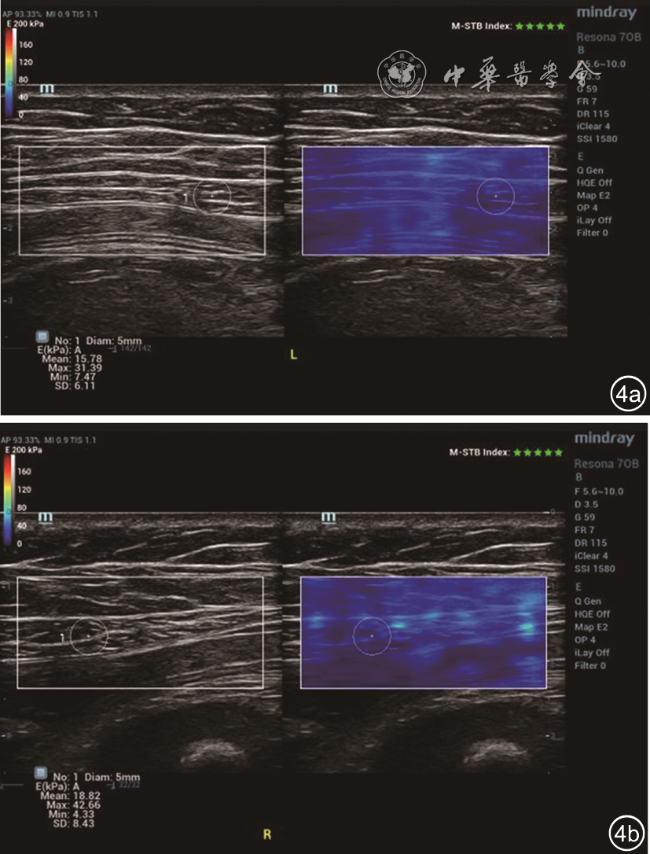

2. 方法:受检者平躺,暴露腹部检查区域,采用横向、纵向、斜向多平面结合方式先进行实时二维灰阶扫查,观察剑突以下至耻骨联合以上的腹直肌情况,测量脐水平、脐上5 cm水平、脐下5 cm水平的双侧腹直肌高回声筋膜内侧缘间的距离,记录为IRD0、IRD+5、IRD-5图12)。二维超声定位双侧腹直肌内侧1~2 cm范围内的部位,嘱患者屏气3~5 s,开启SWE扫查模式,剪切波弹性的量程为0~180 kPa,待图像稳定后冻结,选择感兴趣区域(region of interest,ROI),ROI范围为双侧腹直肌内侧1~2 cm的最大测量面积(不包括腹直肌筋膜),手持探头在检测部位,不施加压力。双幅实时显示功能观察二维图与弹性图,选取ROI,静置3~5 s,保持探头稳定以获得稳定弹性图(M-STB Index:5颗绿星)并保存,观察和记录该区域弹性模量颜色分布特征。仪器自带Q-BOXTM定量测量工具,测量ROI范围内杨氏弹性模量值[平均值(Emean)、最大值(Emax)、最小值(Emin)],每个区域(右侧腹直肌脐水平R0、左侧腹直肌脐水平L0、右侧腹直肌脐上5 cm水平R+5、左侧腹直肌脐上5 cm水平L+5、右侧腹直肌脐下5 cm水平R-5、左侧腹直肌脐下5 cm水平L-5)中部水平测量2次,取平均值(图34)。

图4 28岁初产妇妊娠37+3周,脐上5 cm水平左侧腹直肌剪切波弹性成像(SWE)参数:Emean=15.78 kPa,Emax=31.39 kPa,Emin=7.47 kPa(图a);右侧腹直肌SWE参数:Emean=18.82 kPa,Emax=42.66 kPa,Emin=4.32 kPa(图b)